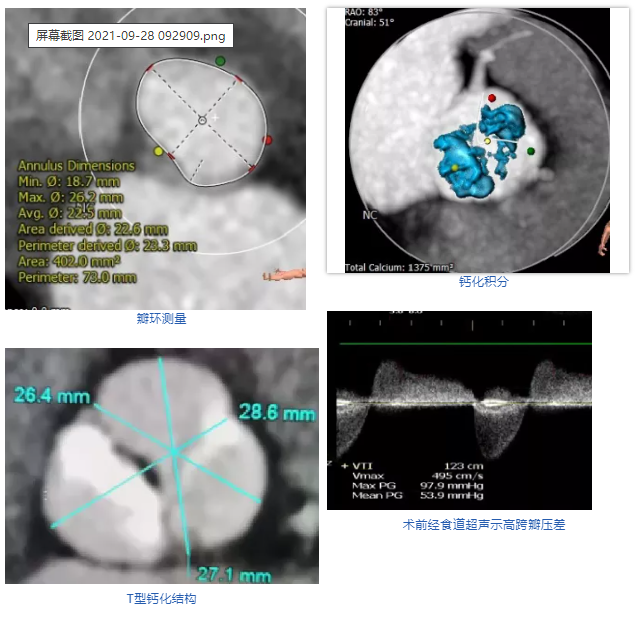

患者女性,75岁,因“反复胸闷、胸痛1年余”入院。超声心动图示主动脉瓣重度狭窄钙化,伴中重度关闭不全。CT显示主动脉瓣为Type 1型二叶瓣,且无冠瓣与左右冠瓣融合嵴形成“T型”钙化结构,属TAVI挑战病例。瓣环平均直径22.5mm,瓣环面积402.0mm²。左冠脉开口高度11.8mm,右冠脉开口高度11.0mm。术前TEE示峰值流速4.9m/s,平均跨瓣压差54mmHg,有强烈手术指征。